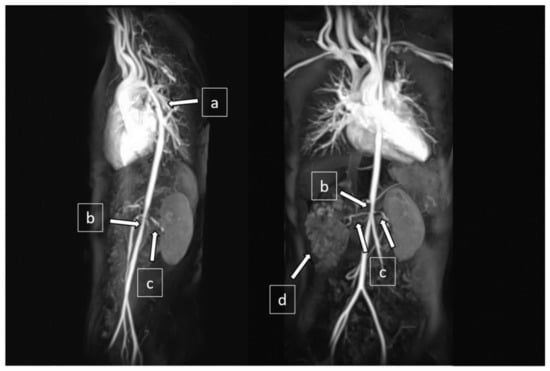

Magnetic resonance angiogram revealed diffuse aortopathy involving the aortic arch (5 mm in diameter at isthmus), thoracic aorta (7 mm), and abdominal aorta (5 mm). The main branches from the aorta were also affected, including bilateral renal artery stenoses (RAS) and narrowed celiac trunk and superior mesenteric artery (2–3 mm in diameter) (Figure 3). The Doppler ultrasound did not show focal stenosis in her common, internal, or external carotid arteries.

Figure 3.

Magnetic resonance angiography (MRA) showed (a) narrowing at the distal aortic arch and descending thoracic aorta, (b) narrowing at the abdominal aorta, (c) bilateral renal artery stenoses, and (d) right cystic kidney.